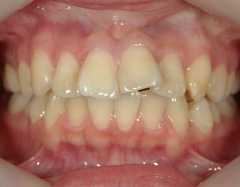

no.6_8296_治療前_右.jpgno.6_8296_治療前_正面.jpgno.6_8296_治療前_左.jpg